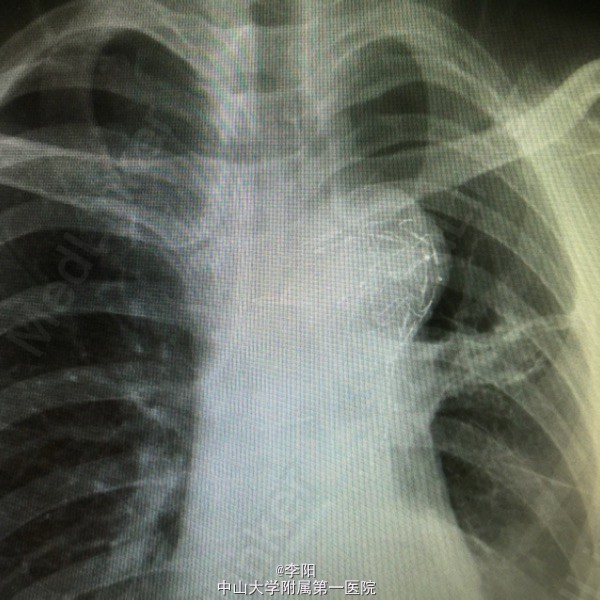

主动脉夹层一例

主动脉夹层

患者一周余前无明显诱因出现腹痛,程度较剧烈,以脐周痛为主,无加重或缓解体位。胸部ct提示主动脉夹层,Debackey 3型